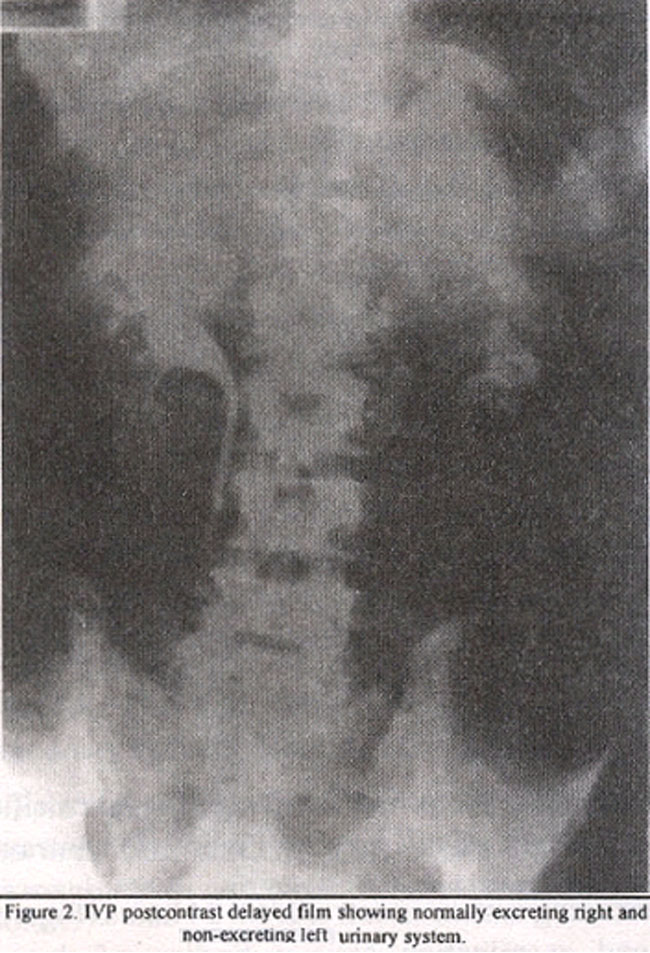

Intravenous pylography showed normally excreting right urinary system with a non-excreting system on left side till 24 hours (Figure

2).